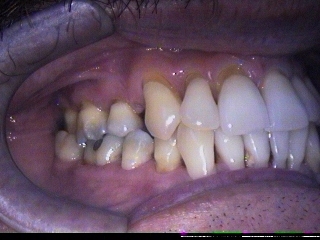

Restaurações de abrasões de tecido

dentário ao nível do colo dental, com resina composta.

DEPOIS